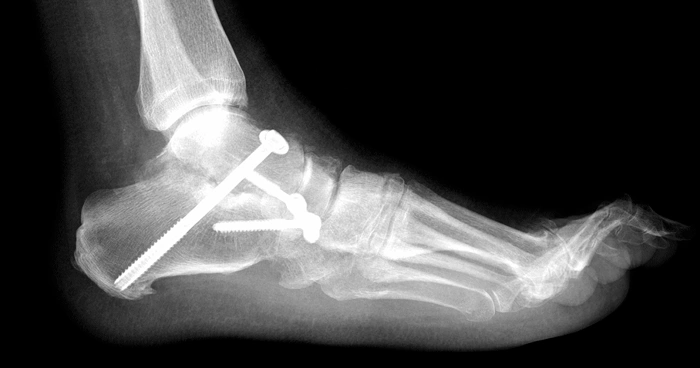

Артродез суставов: полное руководство по операции для возвращения опоры и жизни без боли

Если сустав разрушен артрозом или травмой и причиняет невыносимую боль, артродез может стать решением. Эта статья подробно объясняет суть операции, когда она необходима, как проходит и чего ожидать после для восстановления активной жизни.